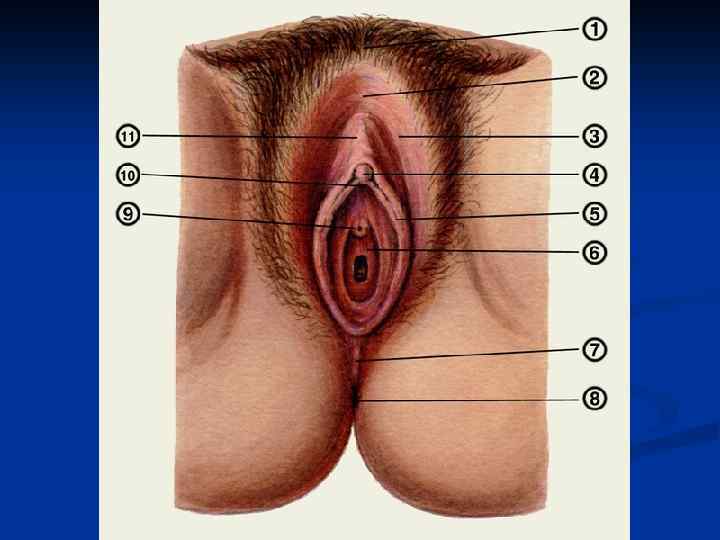

Женские половые органы, organa genitalia feminina

Женские половые органы, organa genitalia feminina